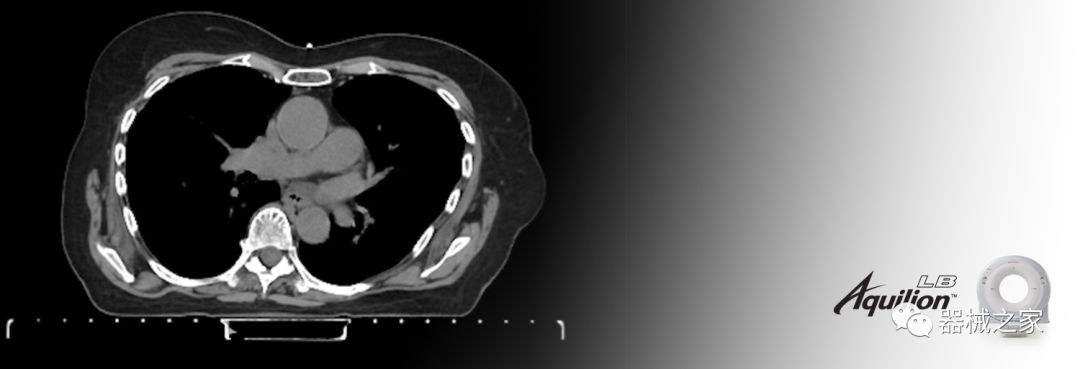

佳能醫(yī)療的Aquilion Lightning 80掃描儀還以緊湊,經(jīng)濟(jì)的包裝提供高質(zhì)量的成像。Aquilion Lightning 80旨在可靠,高效地運(yùn)行,在繁忙的環(huán)境中生成高質(zhì)量的圖像。

兩個CT系統(tǒng)均采用0.5 mm x 80排PUREViSION探測器技術(shù)(可配置并從80-160現(xiàn)場升級),78 cm孔徑,50 cm視野,AIDR(自適應(yīng)迭代劑量減少)3-D和SEMAR(單個)能量金屬神器減少)技術(shù)。

Aquilion LB專為滿足腫瘤學(xué)挑戰(zhàn)而設(shè)計,同時優(yōu)先考慮患者護(hù)理。Aquilion LB的內(nèi)徑為90 cm,能夠幫助復(fù)雜的患者設(shè)置并提高患者的舒適度。CT模擬定位可以輕松鏡像放射治療定位,更加自信。該系統(tǒng)采用0.5 mm x 16排(32層)PUREViSION探測器技術(shù),70 cm視野,AIDR 3D和SEMAR技術(shù)。